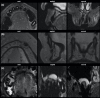

MRI is increasingly used as a diagnostic tool for visualising the dentoalveolar complex. A comprehensive review of the current indications and applications of MRI in the dental specialities of orthodontics (I), endodontics (II), prosthodontics (III), periodontics (IV), and oral surgery (V), pediatric dentistry (VI), operative dentistry is still missing and is therefore provided by the present work.The current literature on dental MRI shows that it is used for cephalometry in orthodontics and dentofacial orthopaedics, detection of dental pulp inflammation, characterisation of periapical and marginal periodontal pathologies of teeth, caries detection, and identification of the inferior alveolar nerve, impacted teeth and dentofacial anatomy for dental implant planning, respectively. Specific protocols regarding the miniature anatomy of the dentofacial complex, the presence of hard tissues, and foreign body restorations are used along with dedicated coils for the improved image quality of the facial skull.Dental MRI poses a clinically useful radiation-free imaging tool for visualising the dentoalveolar complex across dental specialities when respecting the indications and limitations.